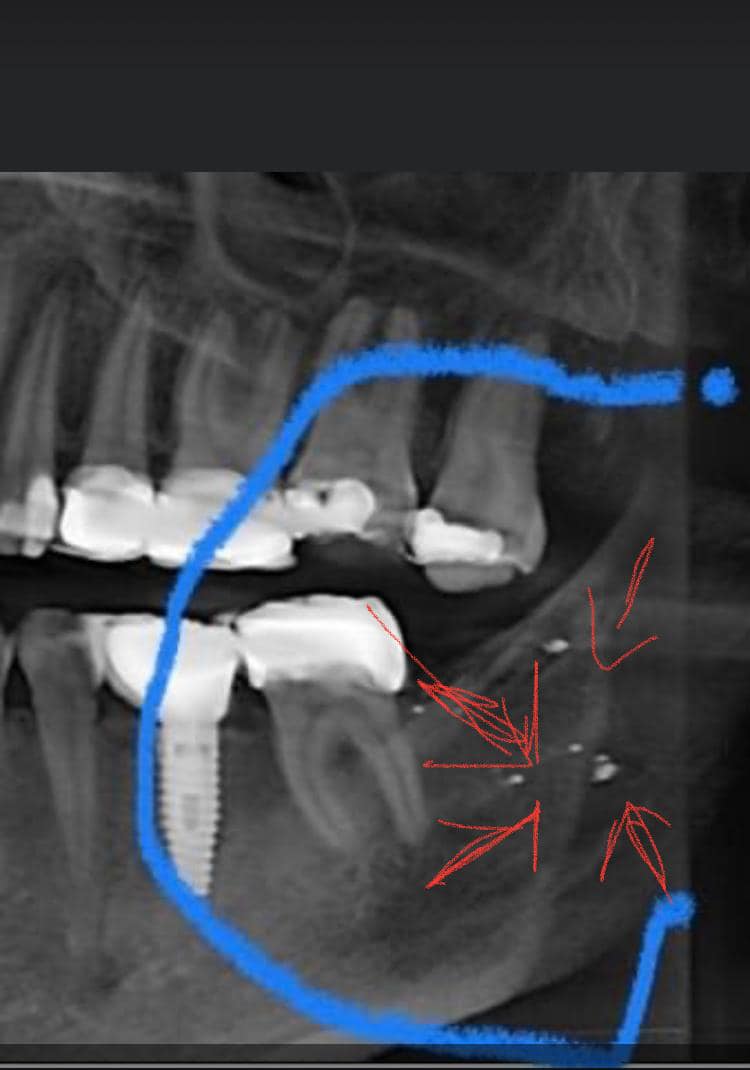

Örnek 1:

Bu özel tarama çekiminde diş eti içinde cıva partikülleri gözüküyor.

Yirmilik dişin çekildiği gün, yanıdaki amalgama müdahale edilmiş. Ve diş eti içine amalgam kıymıklarını da alarak yeniden yapılanmış.

Sonuç bu partikülleri operasyon ile temizlemenin bile mümkün olmadığı…

Cıva partikülleri normal çene röntgenlerinde gözükmez. Üç boyutlu ct matrix 758-68 çekimi gerekir. Çekimi değerlendirmek için de çok işin ehli bir uzman gerekir. Türkiye’de böyle uzaman birine ulaşabilirseniz şanslısınız.

Çoğu çekim bu kadar net değildir. Özellikle diş içinde kalan kıymıkları tespit etmek ciddi uzmanlık gerektiren bir durumdur.

Eskiden sökülmüş bir dişte veya diş etinde, çene kemiğinde sızıntı yapmış amalgam kalıntısı tespiti için : Üç boyutlu 768’li matrix ile dental-CT çekilmesi gerekir.

Çene bölgesinin dikkatli bir teşhis incelemesi kritiktir: Amalgam çıkarılmış hastalarda bile, kronların veya dolguların altında, köklerin ucunda, çene kemiğinde, paranazal sinüslerde ve ayrıca oral mukozal dokularda kalıntı izleri sıklıkla bulunabilir. Bunlar standart X-ışını görüntülerinde görülemez. Bunları görselleştirmek, özel DVT1 tabanlı diyagnostikler veya nadir görülen 768 Matrix ile çok yüksek çözünürlüklü CT2 taramaları gerektirir.